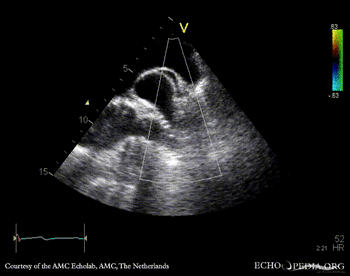

| Courtesy of: AMC Echolab, AMC, The Netherlands | |

| Suprasternal view | Suprasternal view with Color Doppler |